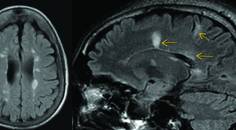

Numerous MRI measures have prognostic value in MS, including the number of T2-hyperintense lesions at baseline—among the most important factors influencing development of disability milestones. In people with CIS/MS who have 0, 1 to 3, 4 to 9, and 10 or more T2 lesions at baseline, the proportions with EDSS 6.0 or more 20 years later were 6%, 18%, 35%, and 45%, demonstrating the relevance of baseline MRI lesion load.25 A large 6-year study of persons with MS who presented with optic neuritis found correlations with subsequent disability accumulation with, in decreasing order of importance, new T2 lesions, new gadolinium-enhancing (Gd+) lesions, baseline enhancing lesions, baseline T2 lesion number, and baseline T2-lesion volume.26,27 A 7-year cohort study of people with CIS showed baseline MRI lesion load was among the most important predictors of developing MS and disability progression. In this study, the presence of 1 to 3, 4 to 9, and more than 10 T2 lesions independently correlated with 5.1-, 7.5-, and 11.3-times increased risk of developing CDMS. Having 10 or more T2 lesions was associated with a nearly threefold elevated risk of disability progression.2

Having infratentorial lesions at baseline is associated with future disability accumulation in CIS or RIS. In a small study of 42 people with CIS followed for 8.7 years, having 2 or more infratentorial lesions at baseline increased the risk of an EDSS score of 3.0 approximately sixfold.32 A larger study of 246 people with CIS observed for 8 years revealed that those with infratentorial lesions within 3 months of onset had a 3.3-times higher risk of conversion to CDMS and a 2.4-times higher likelihood of reaching EDSS score 3.0.33 Similarly, in RIS, there may also be prognostic value of baseline infratentorial lesions. Although an initial 5-year follow-up study did not show predictive value of an infratentorial lesion in developing an initial demyelinating event, a 10-year follow-up study showed baseline infratentorial lesions are predictive of conversion to MS.3,4

A higher number of spinal cord lesions at baseline has been associated with a higher risk of relapse over approximately 3 years.34 In those with CIS, baseline spinal cord lesions and new spinal cord lesions at 1 year independently elevate the risk of developing MS by 4.7 and 5.7 times after 15 years, respectively.31 The presence of cervical or thoracic cord lesions raises the risk of a first clinical event by threefold according to a 5-year cohort study of RIS,3 and the prognostic value persisted in a 10-year follow-up study.4

T1-hypointense lesions or T1-black holes are identifiable on conventional MRI and known to be associated with higher disability in MS.35 A meta-analysis that pooled 27 studies comprising 1,919 cases showed a moderate correlation between T1 hypointense lesion volume and EDSS score.35 T1 lesion volume, however, can be difficult to ascertain in clinical practice. Development of T1 lesions on subsequent MRI has not been definitively validated as useful in clinical practice; therefore, this measure is not used routinely.26

Whole brain atrophy or atrophy of smaller structures affected by MS in the CNS (eg, brain substructures and spinal cord) are associated with clinical disability in numerous studies.36,37 Whole-brain atrophy is associated with cognitive impairment and mood disturbance,22 and spinal cord cross-sectional area and gray matter atrophy correlate with clinical disability.38,39 Whole-brain atrophy has also been widely used in phase 3 clinical trials, and there is a clear association with clinical disability and treatment effect.36 Despite their clinical relevance and use in clinical trials, however, no quantitative measures of atrophy are widely used in clinical practice because of several obstacles, including the need for specific MRI sequences, time and technical expertise needed to utilize volume quantification software, and lack of clear guidelines for use in clinical practice, among other challenges.40